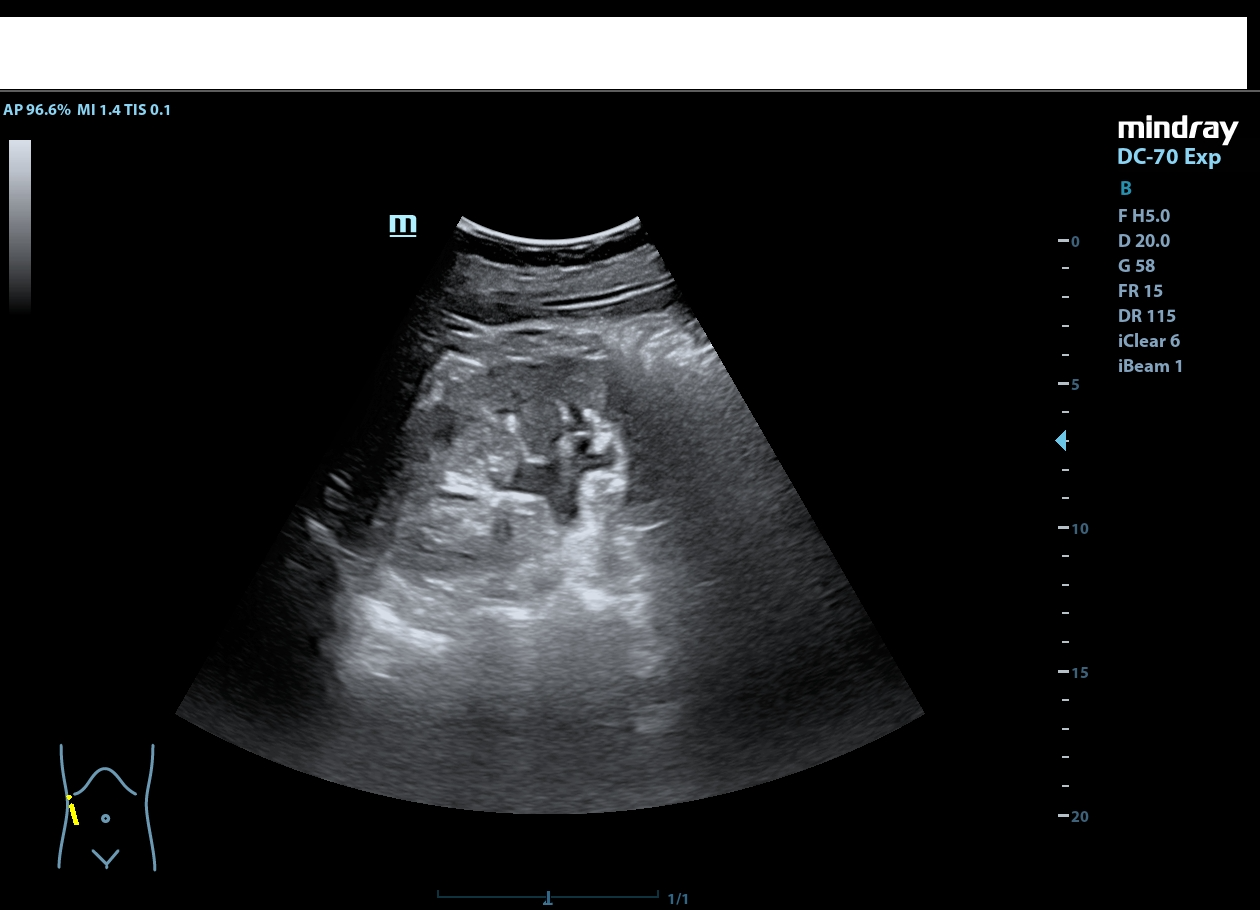

Riñón derecho de ecoestructura conservada, con dilatación pielocalicial grado I. Riñón izquierdo con adelgazamiento cortical y ureterohidronefrosis grado IV, sin poder localizarse el origen de la obstrucción, ausencia de jet ureteral izquierdo. Hallazgos sugestivos de síndrome de la unión pieloureteral.